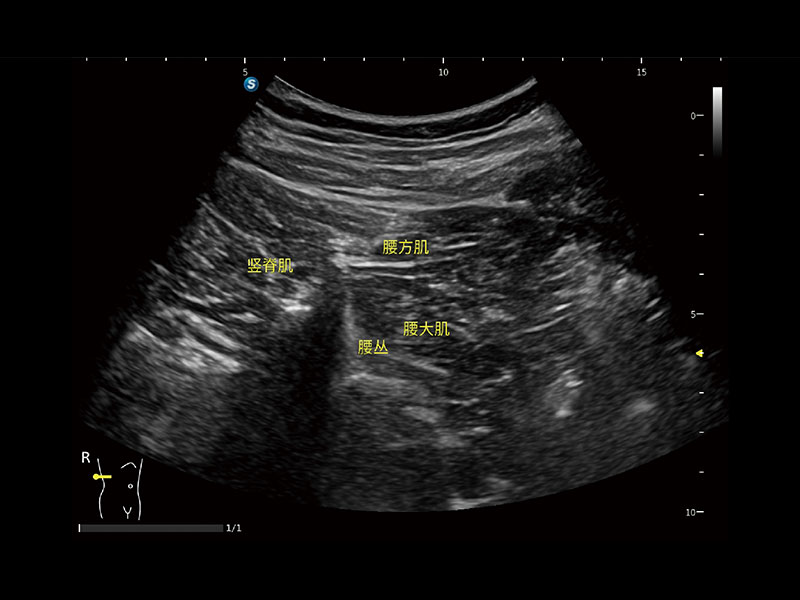

E11搭载了丰富的自动化测量工具,以及专为POC科室定制的高级功能;同时配备了为急诊医师量身打造的 SonoFast急重症超声流程,以帮助临床医生最大限度的提升工作效率